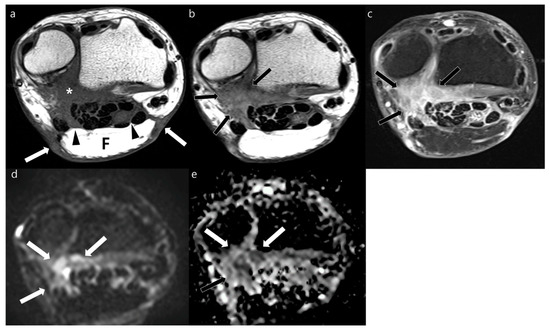

3.2. Morphology of Recurrent Tumors

3.3. MRI Signal Intensity of Recurrent Tumor

3.4. Diagnostic Performance of MRI Features for Diagnosing Local Recurrence

3.5. Post hoc Analysis